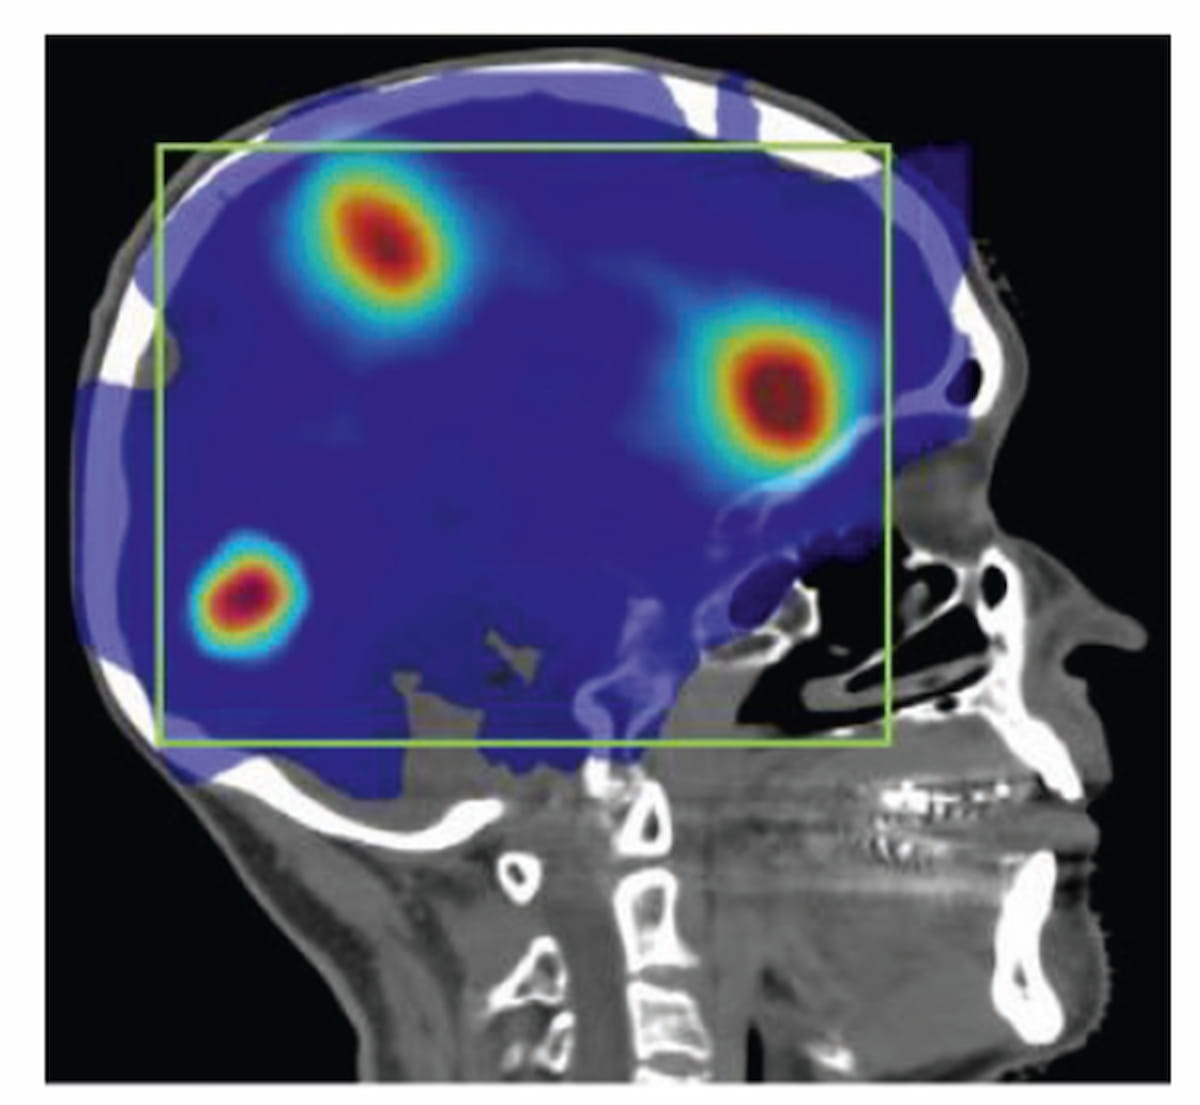

Sixty-five percent of patients with newly diagnosed high-risk prostate cancer may have extraprostatic extension on MRI, and PSMA PET/CT findings suggest those with Gleason scores of eight or higher have more than double the risk of metastasis, according to a new study presented at the European Congress of Radiology (ECR).